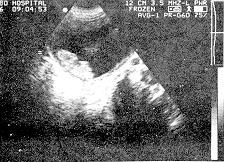

体检:腹平软,肝脾未触及。膀胱浊音界位于耻骨上三横指,轻压痛。双肾区无叩击痛。尿常规:蛋白+、红细胞、潜血。膀胱逆行造影检查,见膀胱三角区呈现大小不等蜂窝样充盈缺损,有分叶,膀胱顶部充盈光滑整齐。B超检查:膀胱充盈,径线53 mm×43 mm,膀胱壁不连续,于膀胱三角区见16 mm×14 mm不规则的增强区,边界不整,膀胱右后壁见一30 m×20 mm大小团块,内部回声增强,周边不光整,向膀胱内凸起,后方无声影,不随体位变动而移动(见附图)。双肾轮廓清,径线正常,皮质及集合部未见明显异常。诊断为膀胱肿瘤。后经上级医院手术,确诊为膀胱三角区及后壁横纹肌肉瘤。

附 图